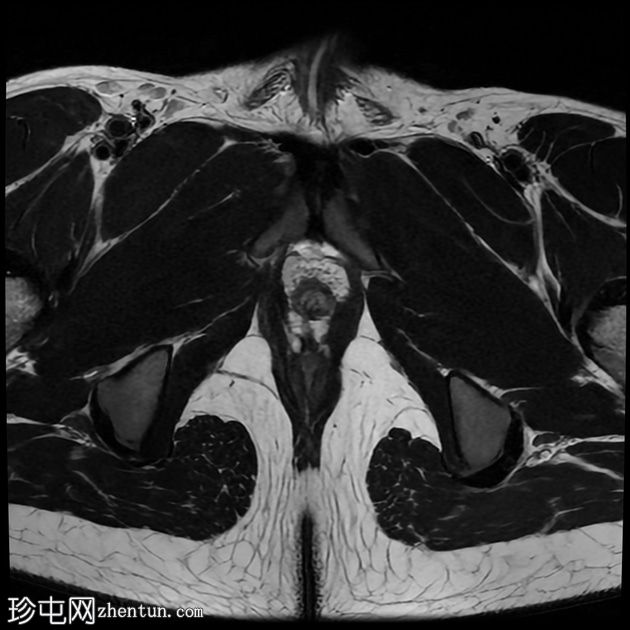

轴位

T1加权像

前列腺大小为32.8 x 41.5 x 34.7 mm(前后径 x 宽度 x 头尾径),体积为25.88 ml,属于正常范围。前列腺中央可见一逗号状囊性占位性病变,大小为17.3 x 12.1 x 9.3 mm(头尾径 x 前后径 x 宽度)。可见囊肿与前列腺尿道相通。囊内未见可疑内容物——具体而言,未见囊内出血或碎屑——弥散加权成像结果为阴性,提示无囊内感染。

动态增强扫描显示前列腺呈均匀强化,未见可疑的周边部或移行区异常。精囊正常。膀胱正常。盆腔内未见可疑淋巴结。

本例为一例发生于青年人的单纯性逗号状中央型前列腺内囊肿。

根据囊肿位于前列腺中央或中线(精阜水平)、患者年龄(二十岁左右)以及无前列腺外延伸和明显的尿道交通,前列腺囊肿是首选诊断。苗勒氏管囊肿通常难以排除。患者的年龄、无前列腺外延伸以及疑似尿道交通使该诊断的可能性降低。